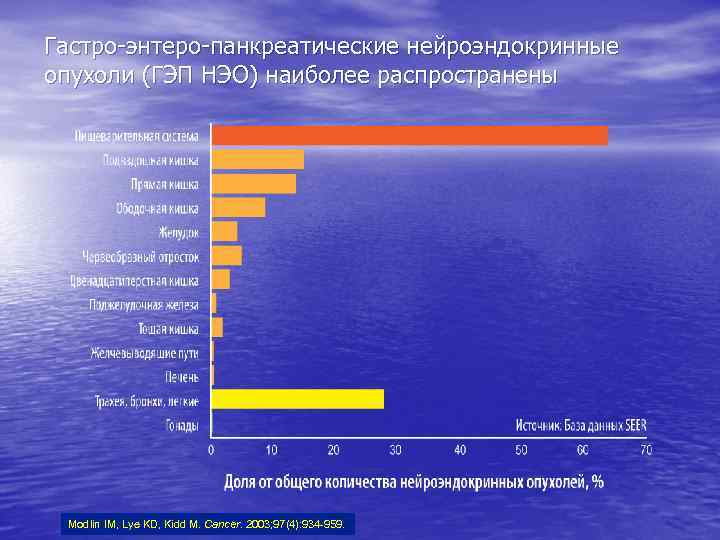

Гастро-энтеро-панкреатические нейроэндокринные опухоли (ГЭП НЭО) наиболее распространены Modlin IM, Lye KD, Kidd M. Cancer. 2003; 97(4): 934 -959.